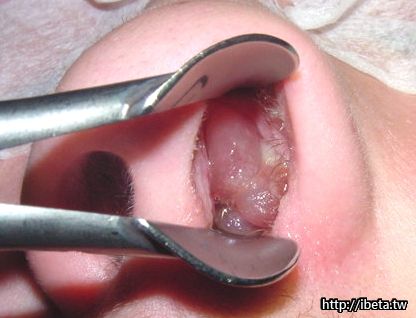

很大的鼻息肉建議開刀拿掉,鼻息肉多伴隨著慢性鼻竇炎.至於下鼻甲肥大則不是病態組織, 它是鼻腔裡的正常組織, 只是若長的太大,則會妨礙呼吸.下鼻甲切除(turbinectomy)是手術選項.